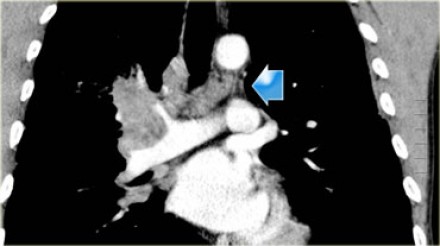

N2 - стадия На данном снимке N2-стадия у пациента с ипсилатеральной медиастинальной

или субкаринной лимфаденопатией. |

N3 - стадия При N3-стадии визуализируют контралатеральную медиастинальную или контралатеральной хиларную лимфаденопатию или лимфааденопатию надключичных узлов. Считается нерезектабельным состоянием. |

На снимках представлены два пациента с раком легких и лимфаденопатией на

стороне поражения и контралатеральной стороне. |

N3-стадия При N3-стадии визуализируют контралатеральную медиастинальную или контралатеральной хиларную лимфаденопатию или лимфааденопатию надключичных узлов. Считается нерезектабельным состоянием. |